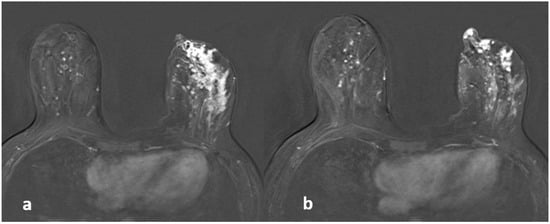

Figure 5.

A 42-year-old woman with histopathologically proven invasive ductal carcinoma involving the left breast. (a,b) Contrast-enhanced subtracted images show segmental enhancement with clumped internal enhancement pattern extending into the nipple in the left breast.